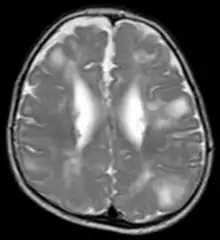

لدى حوالي 50% من المرضى المصابين بالتصلب الحدبي المعقد صعوبات في التعلم تتراوح من معتدلة إلى خطيرة، وذكرت الدراسات أن من بين 25% و 61% من المصابين يجمعون معايير التشخيص لمرض التوحد مع نسبٍ عالية تُظهر صفات مرض اضطراب النمو المتفشي بشكل أوسع، وقد ذكرت دراسة عام 2008 أن 10% من مرضى التصلب الحدبي المعقد لديهم سلوك مؤذٍ لأنفسهم، فيمكن أن تحدث سلوكيات آخرى كاضطراب فرط الحركة وتشتت الانتباه والعدوان والاندفاعات السلوكية والوسواس القهري، ويرتبط انخفاض معدل الذكاء أكثر مع الدماغ الذي صور بالرنين المغناطيسي.

تشمل مظاهر التصلب الحدبي داخل القحف العقيدات تحت البطانة العصبية و الدرنات القشرية أو تحت القشرية. وعادةً تكون الدرنات ثلاثية التكوين مع رأس حاد بإتجاه البطينين والتي يُعتقد أنها تمثل بؤرة لانتقال الخلايا العصبية الطبيعية، وقد تخمل الإشارة T2 غير الطبيعية في مرحلة البلوغ ولكنها ستكون واضحة في تحاليل الأنسجة، من الممكن أن يتعرض مرضى التصلب الحدبي خلال التصوير بالرنين المغناطيسي لعلامات أخرى تتطابق مع انتقال الخلايا العصبية الطبيعية كمساحات المادة البيضاء الشعاعية عالية القوة على T2WIوالمادة الرمادية المغايرة. تتكون العقد تحت البطانة العصبية من خلايا غير طبيعية وخلايا الورم الدبقي و خلايا شاذة متعددة النواة التي لاتحدد أصل الدبقية أو العصبوني، ولاتوجد هناك أنسجة عصبية متوسطة، فهذه العقد تميل للتكلس بحسب عمر المريض، وتعتبر العقدة التي تنمو وتكبر بشكل ملحوظ مع مرور الوقت مشبوهه لتتحول إلى أورام نجمية ضخمة تحت البطانة العصبية (SGEA)، وعادةً تتطور الأورام النجمية الضخمة تحت البطانة العصبية في منطقة ثقب مورنو وفي هذه الحالة فهو خطر لتطور موهة الرأس الأنسدادي، فالدرجة المتغيرة التي تدل على توسع البطين إما تكون بسبب الأنسدادي ( على سبيل المثال بسبب عقدة البطانة تحت العصبية في منطقة ثقب مورنو) أو أسباب مجهولة في الطبيعة.